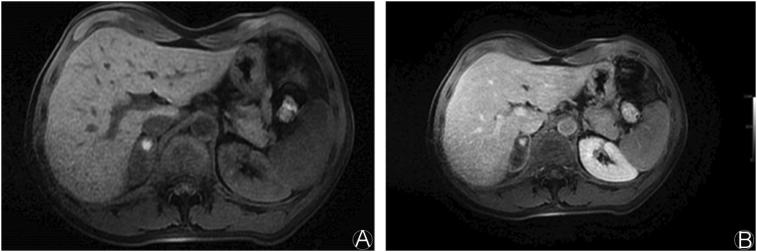

Adrenal hemorrhage following blunt abdominal trauma is extremely rare. Most of the lesions are unilateral and right sided. Although often asymptomatic, life-threatening adrenal insufficiency may develop in the bilateral adrenal gland hemorrhage. Isolated adrenal injuries are very rare. They are often associated with other organ injuries. The mortality rates of patients range from 7% to 32%. In this report, we present the computed tomography and magnetic resonance imaging findings of unilateral adrenal hemorrhages in two patients with a history of fall from a height.

钝性腹部创伤后肾上腺出血极为罕见。大多数病变为单侧且位于右侧。虽然通常无症状,但双侧肾上腺出血可能会发展为危及生命的肾上腺功能不全。孤立性肾上腺损伤非常罕见。它们常与其他器官损伤相关。患者的死亡率在7%至32%之间。在本报告中,我们展示了两名有高处坠落史患者单侧肾上腺出血的计算机断层扫描和磁共振成像结果。